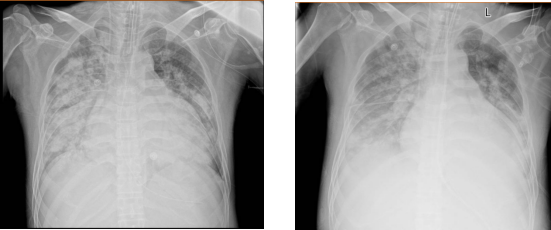

近日,深圳28岁男子小刘高烧不退到深圳市人民医院就医,经检查他感染了甲型流感病毒,入院后病情加重,最后转入ICU治疗。胸片报告显示,他的肺部出现了严重的“大白肺”,体内出现了泛耐药鲍曼不动杆菌。

刚入院1周的肺部影像。图源:深圳市人民医院

医院迅速开展噬菌体疗法。小刘的“大白肺”经过5天的治疗,基本恢复成正常状态。又过了2天,他成功撤离呼吸机并拔除气管插管,痰培养显示,鲍曼不动杆菌也已经转阴,最终休养了一个礼拜后顺利出院了。医生表示当传统抗生素在“超级细菌”面前节节败退,噬菌体疗法为重症感染患者打开了一扇希望之窗。